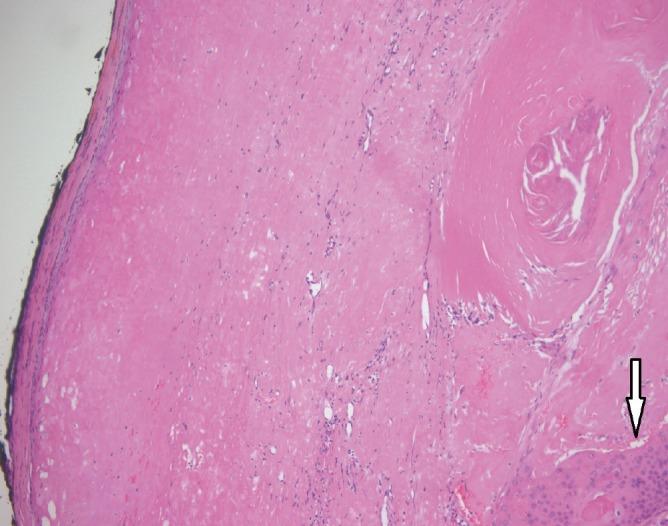

Squamous Cell Carcinoma Arising from an Epidermal Inclusion Cyst.

https://cdn.ncbi.nlm.nih.gov/pmc/blobs/d609/4738116/9a75934d012e/aps-43-112-g001.jpg